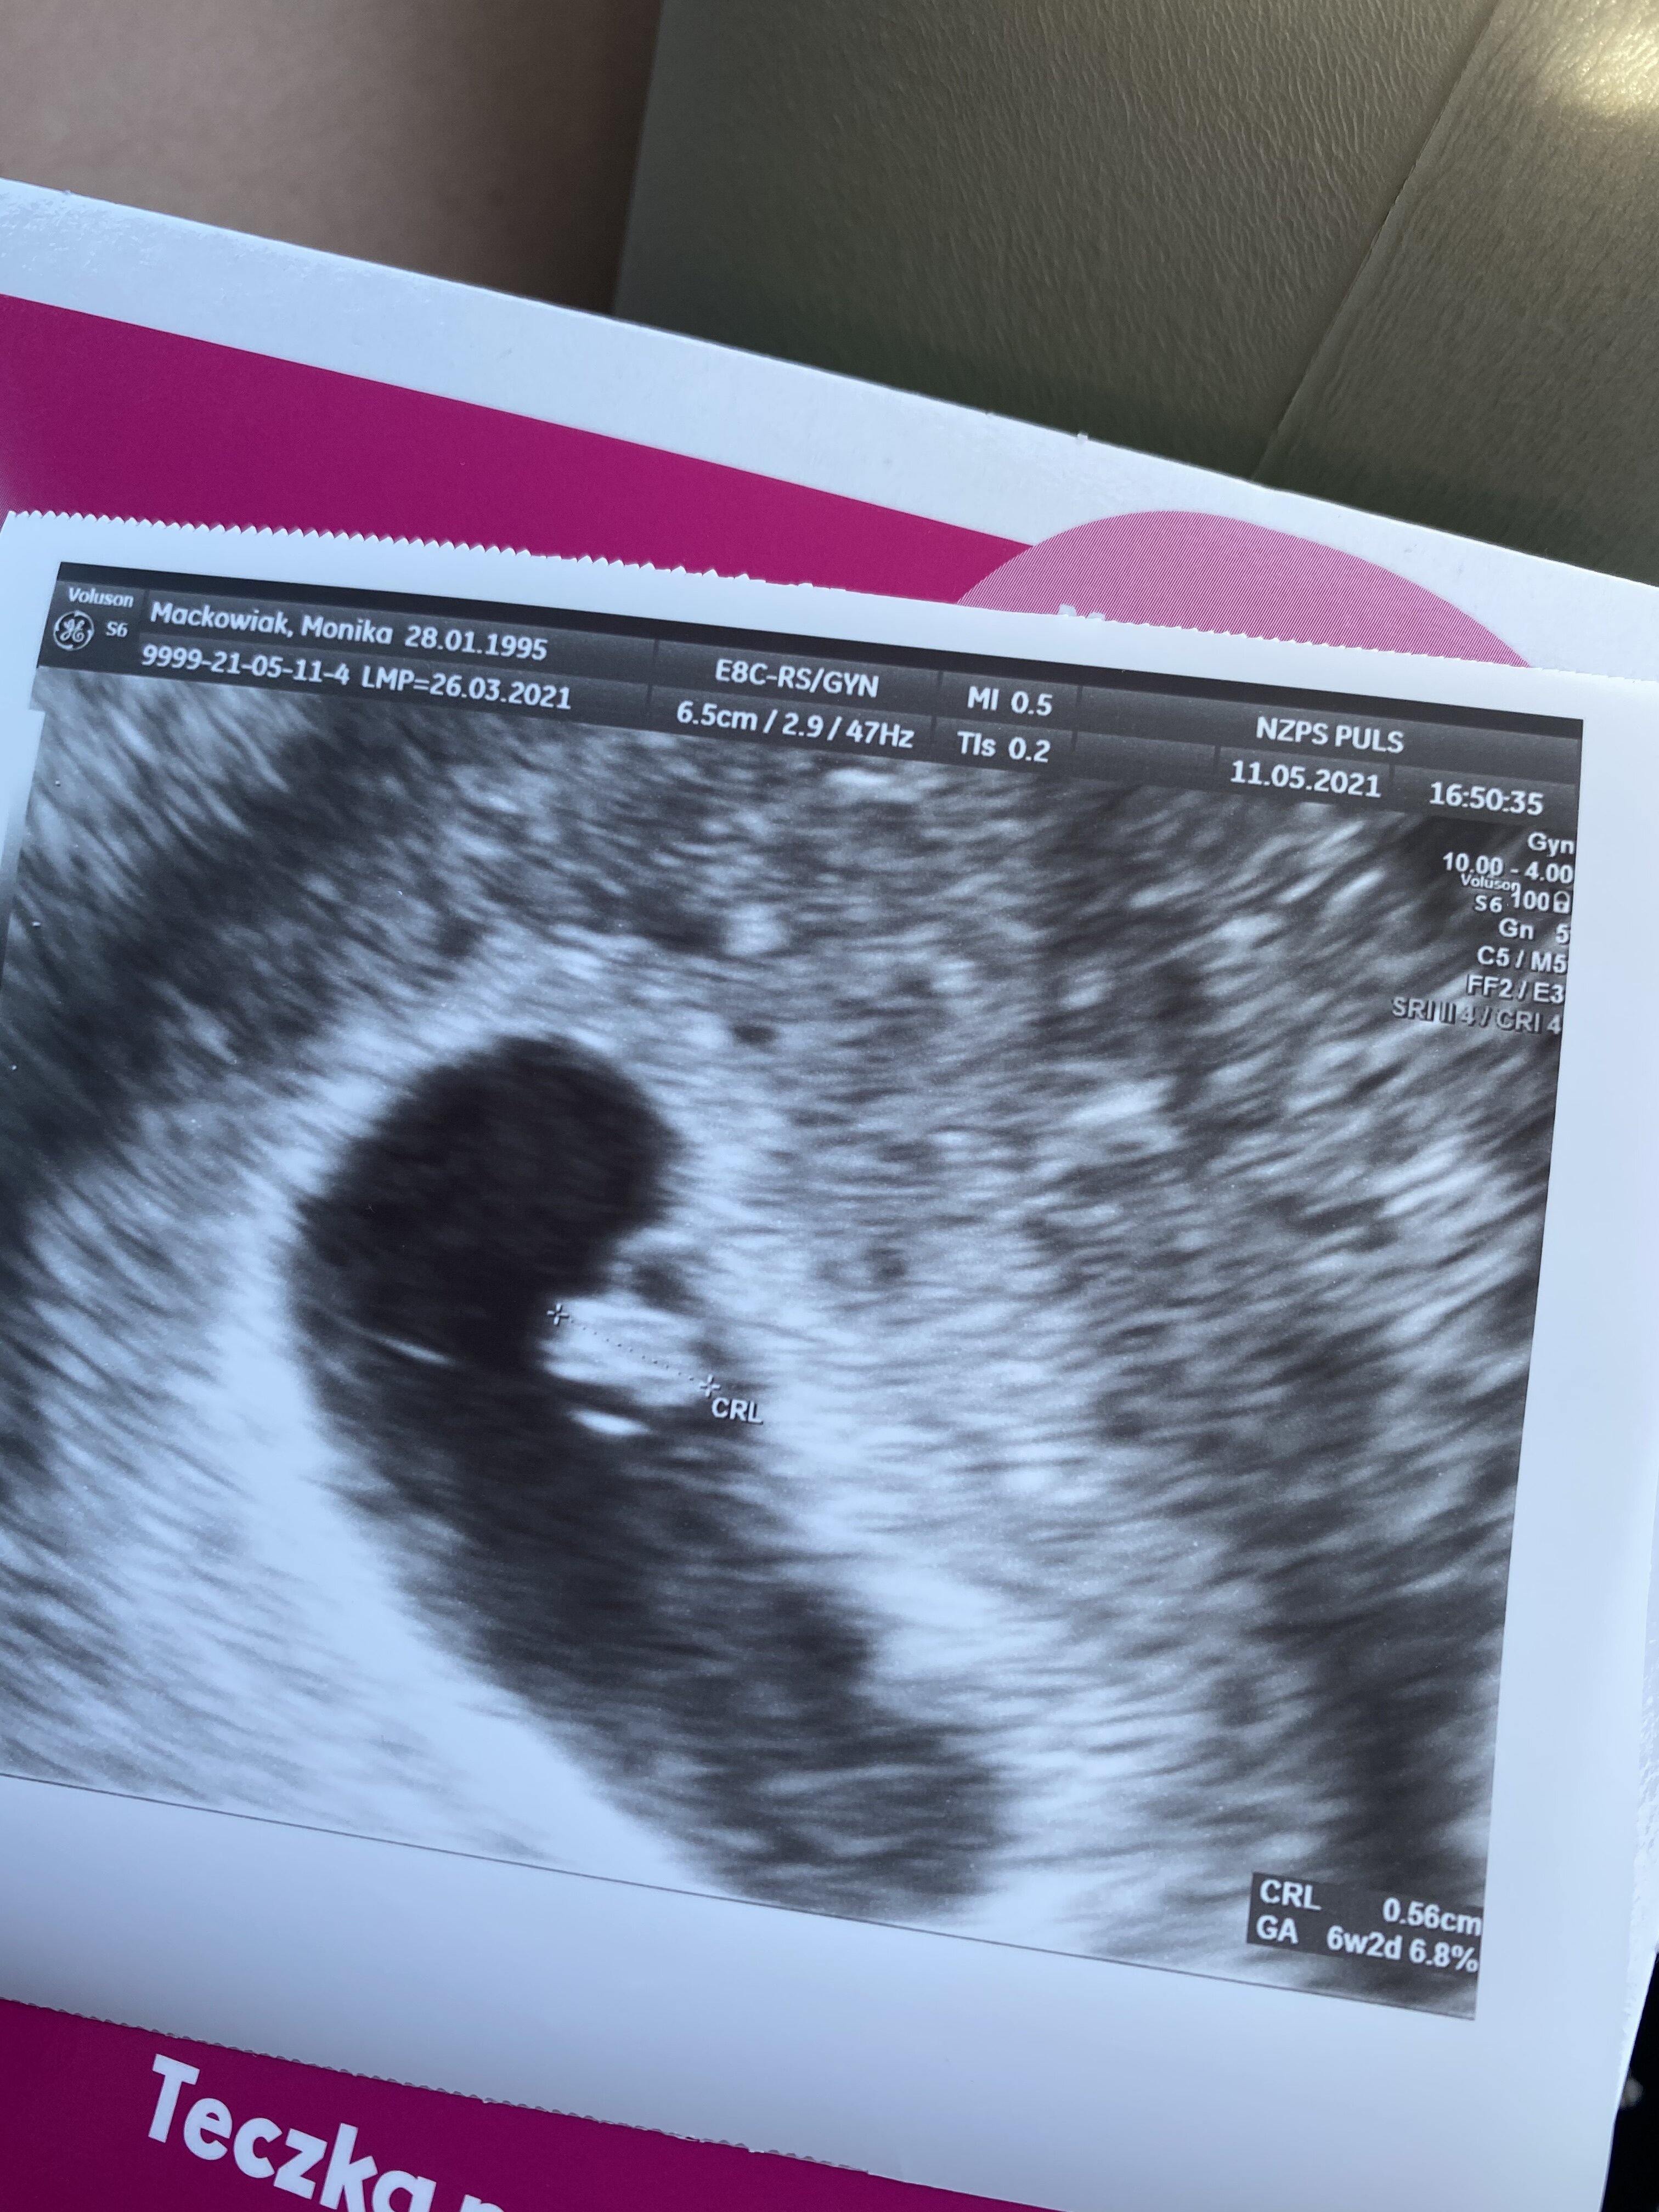

Trzymam kciuki i czekam na dobrą wiadomość [emoji846] który masz teraz tydzień?Nie wytrzymałam dziewczyny i poszłam dziś na wizytę. OM 6+4 a z USG wychodzi 6+2. Biło!!!! Biło!!!! [emoji175][emoji175][emoji175][emoji175]

Nie wytrzymałam dziewczyny i poszłam dziś na wizytę. OM 6+4 a z USG wychodzi 6+2. Biło!!!! Biło!!!! [emoji175][emoji175][emoji175][emoji175]